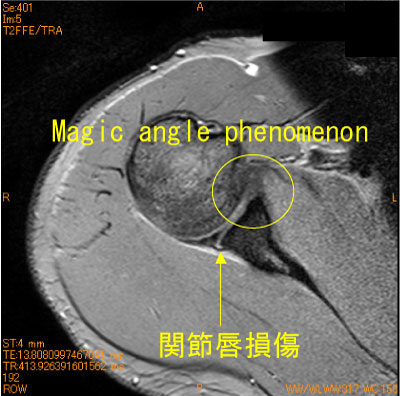

SLAP lesionが注目も集めているが、後方関節唇損傷もありうる。この部位ではT2*WIでもMagic angle phenomenonが生じない。

前方の関節唇にはmagic angle phenomenonが生じている。